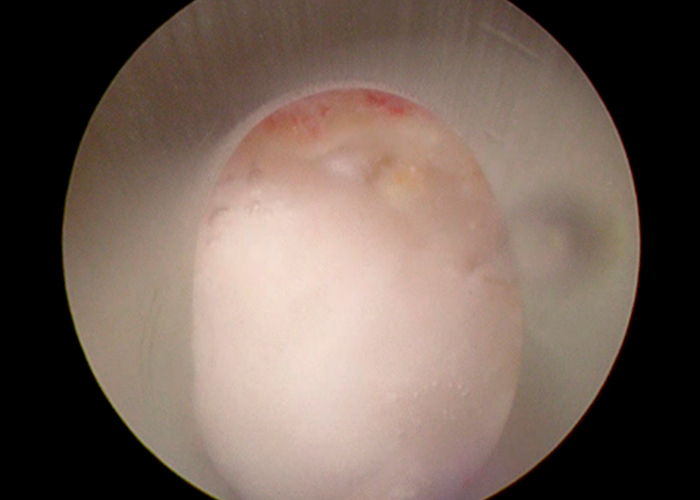

Preoperatorio

Paciente que acude a consulta por estenosis de canal, central con clínica de claudicación neurógena severa a partir de los 50 metros.

El paciente aquejaba de mucho dolor en ambos MMII por igual, reflejos disminuidos tanto aquíleo como rotuliano.

preoperatorio-estenosis-de-canal-instituto-cac